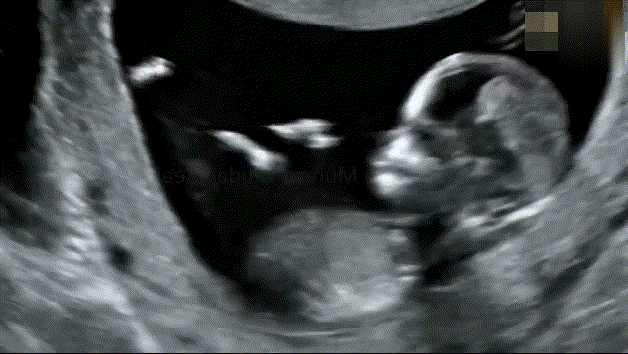

宝宝每天在妈妈的肚子里做什么[思考]?[期待]做得最多的:睡觉胎儿在妈妈肚子里都